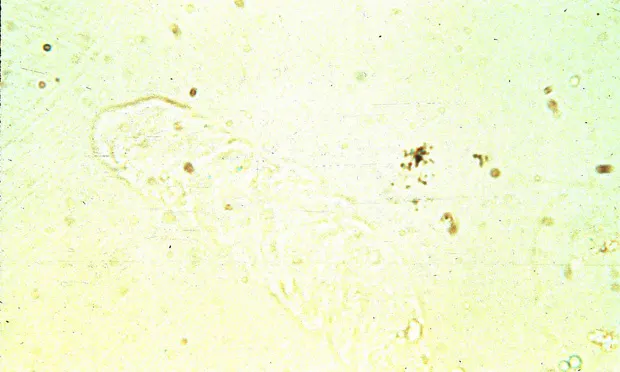

Featured Image

Photomicrograph of a hyaline cast from the urine sediment of a dog with protein-losing nephropahty.